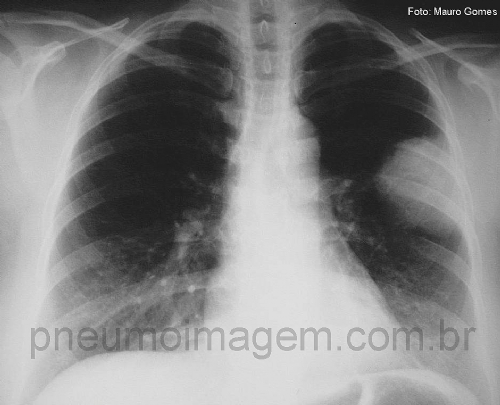

Veja imagens de pneumonia causada pelo S. pneumoniae no PneumoImagem,

clicando aqui.